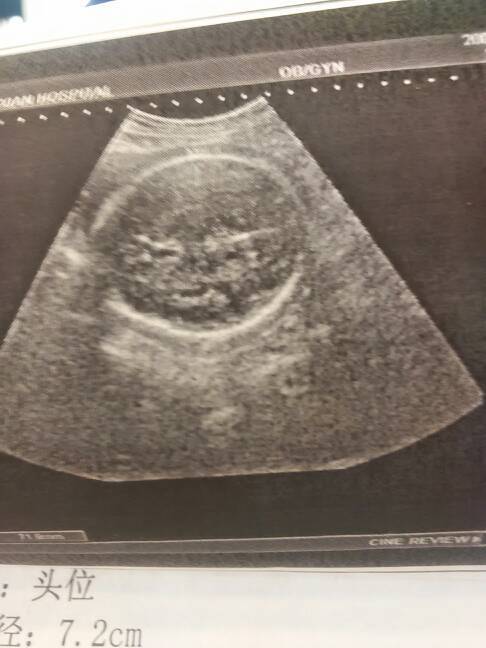

刚做完产检,医生说宝宝还行,但是这个还行不知道是怎么个还行法,说我气血不足,身体太虚,血压低,拿了 刚做完产检,医生说宝宝还行,但是这个还行不知道是怎么个还行法,说我气血不足,身体太虚,血压低,拿了四百块钱的药,谁能看清楚,这到底男孩女孩? 点击展开 若相惜、卟弃_mP1X 2015-02-06 15:06 为您推荐: 其他回答 看不出来吧 马宝宝蛋儿 2015-02-06 17:21 多吃点好的补补 ら.⒉O味道狠甜 2015-02-06 15:46 看不清楚奥 铭岳 2015-02-06 15:27 吃肉、鱼、牛肉、红枣。 七缘香 2015-02-06 15:22 祝宝妈好孕 135*****835_FQkz 2015-02-06 15:12 加载更多 相关问题 医生叫我十四周开始吃,我贫血,气血虚,胃也不好,这个牌子吃了好吗?有更适合的麻烦介绍一下 我想问有专冶中医调理的医生告诉我怎样气血不足,母乳下降,怎样快下奶的食谱有哪些! 停经四十多天了!孕蘘9x5mm大小!医生说孕蘘小怎么办???本人气血不足!怎么办??是不是发育不好